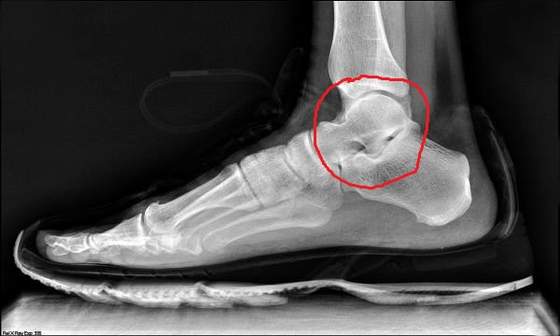

mam teraz chodzic o kulach zeby bardziej kosci nie skruszyc i czekac na termin operacji. Wrzucil mnie jako urgent wiec pewnie ze dwa trzy tygodnie....